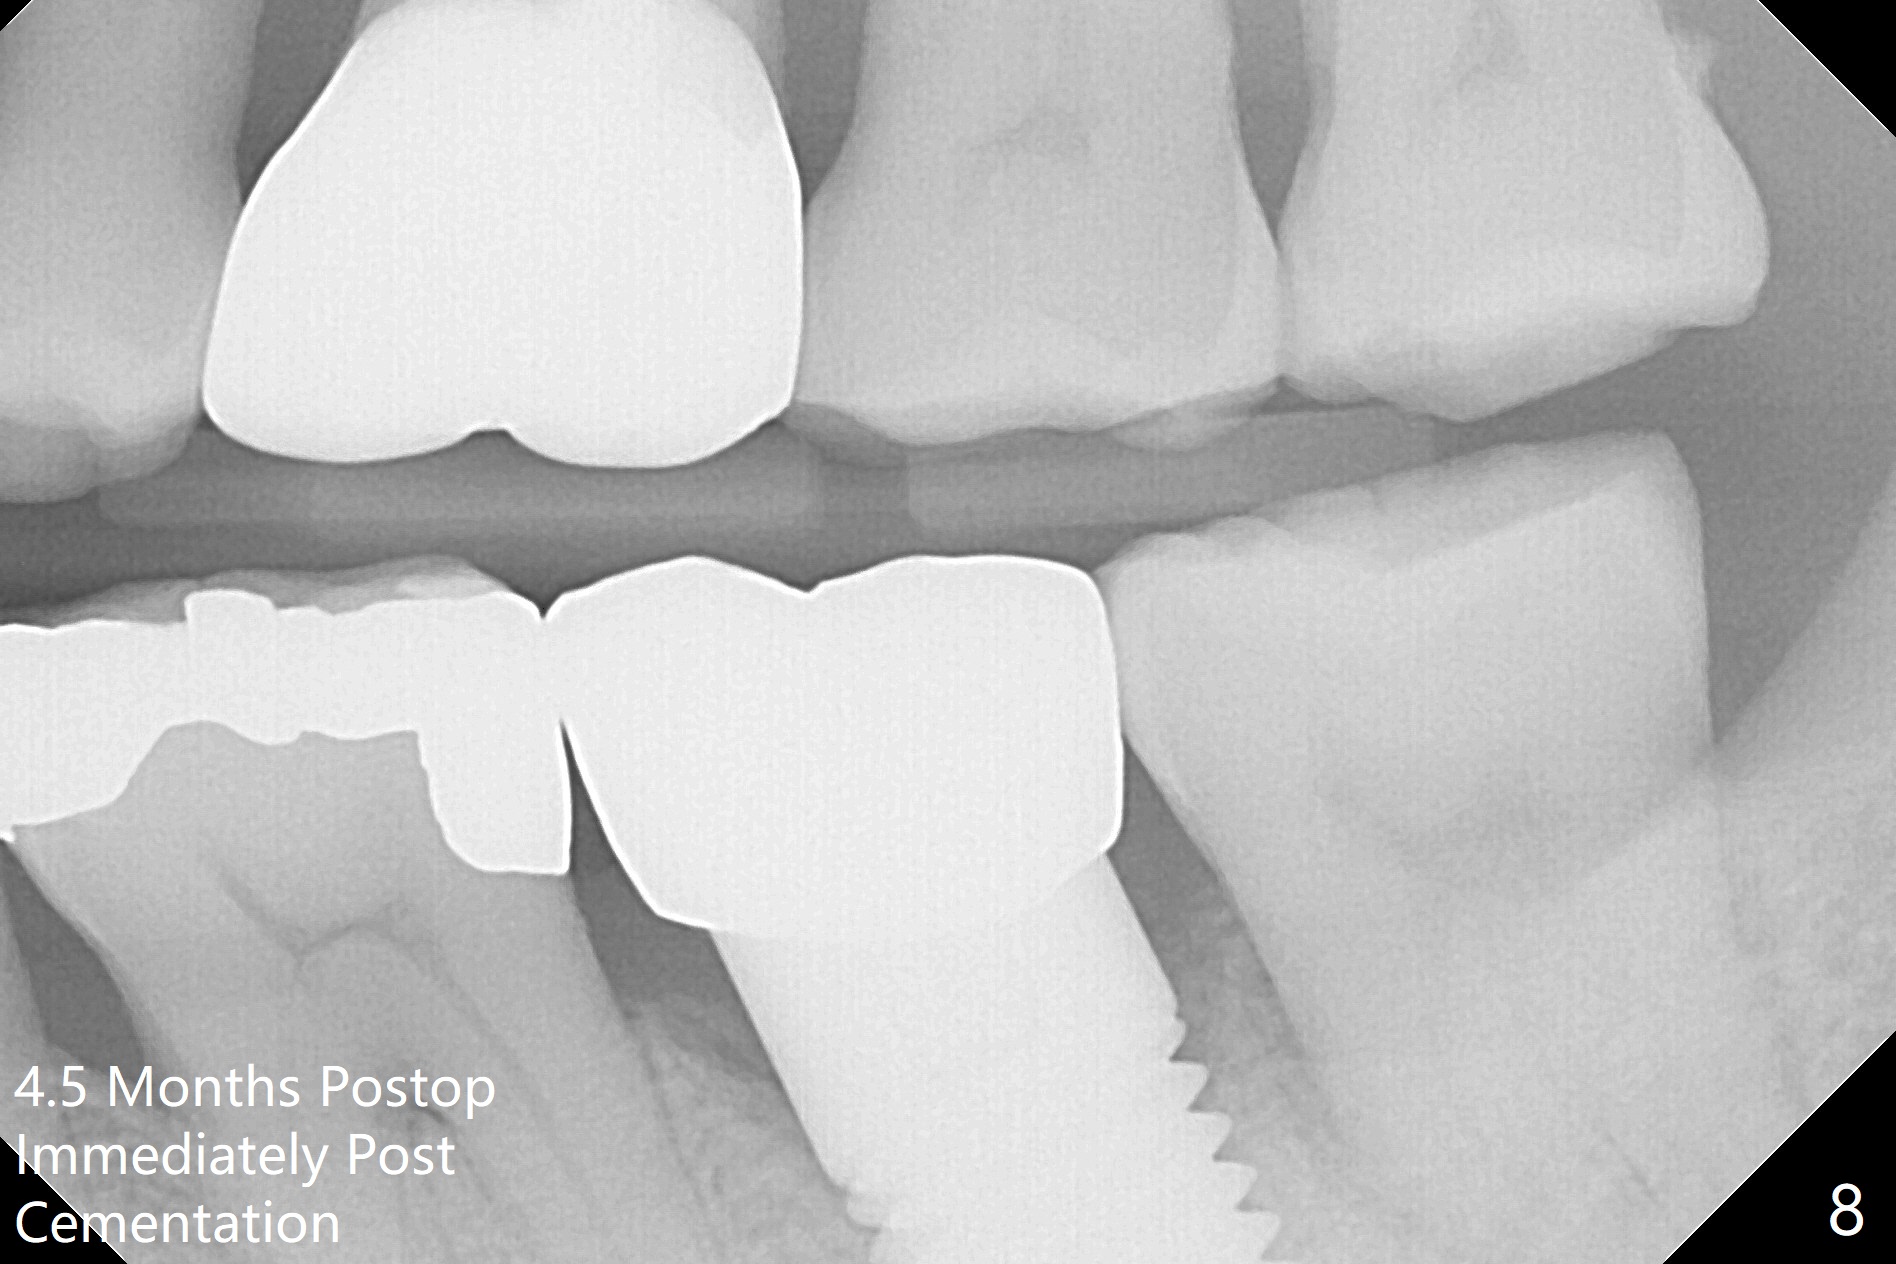

When the mobile tooth #18 with apical granulation tissue is extracted, the socket is large and long (close to the Inferior Alveolar Canal (Fig.2,3 red dashed line). Without drilling, a 7 mm bone level tap does not obtain stability. A 8x17 mm tapered tap reaches the bottom of the socket with minimal stability, but coronally it is close to the tooth #32 (Fig.1). When a 7x14 mm cylindrical tap is placed, it is shy of the bottom of the socket (Fig.2 *), but the trajectory improves. A 7x14 mm tissue-level implant is placed with ~45 Ncm (still not secure) with Vanilla graft placed mainly distolingually (Fig.3). With the large implant, the socket is closed 8 days postop (Fig.4). The soft and hard tissues appear to heal 3 months postop (Fig.5,6). A healing abutment (Fig.7 H) is placed to push the mesial papilla mesially (*). Two weeks later impression is taken with ease because of the healing abutment. There is no bone loss 4.5 months postop (immediately post cementation, Fig.8).